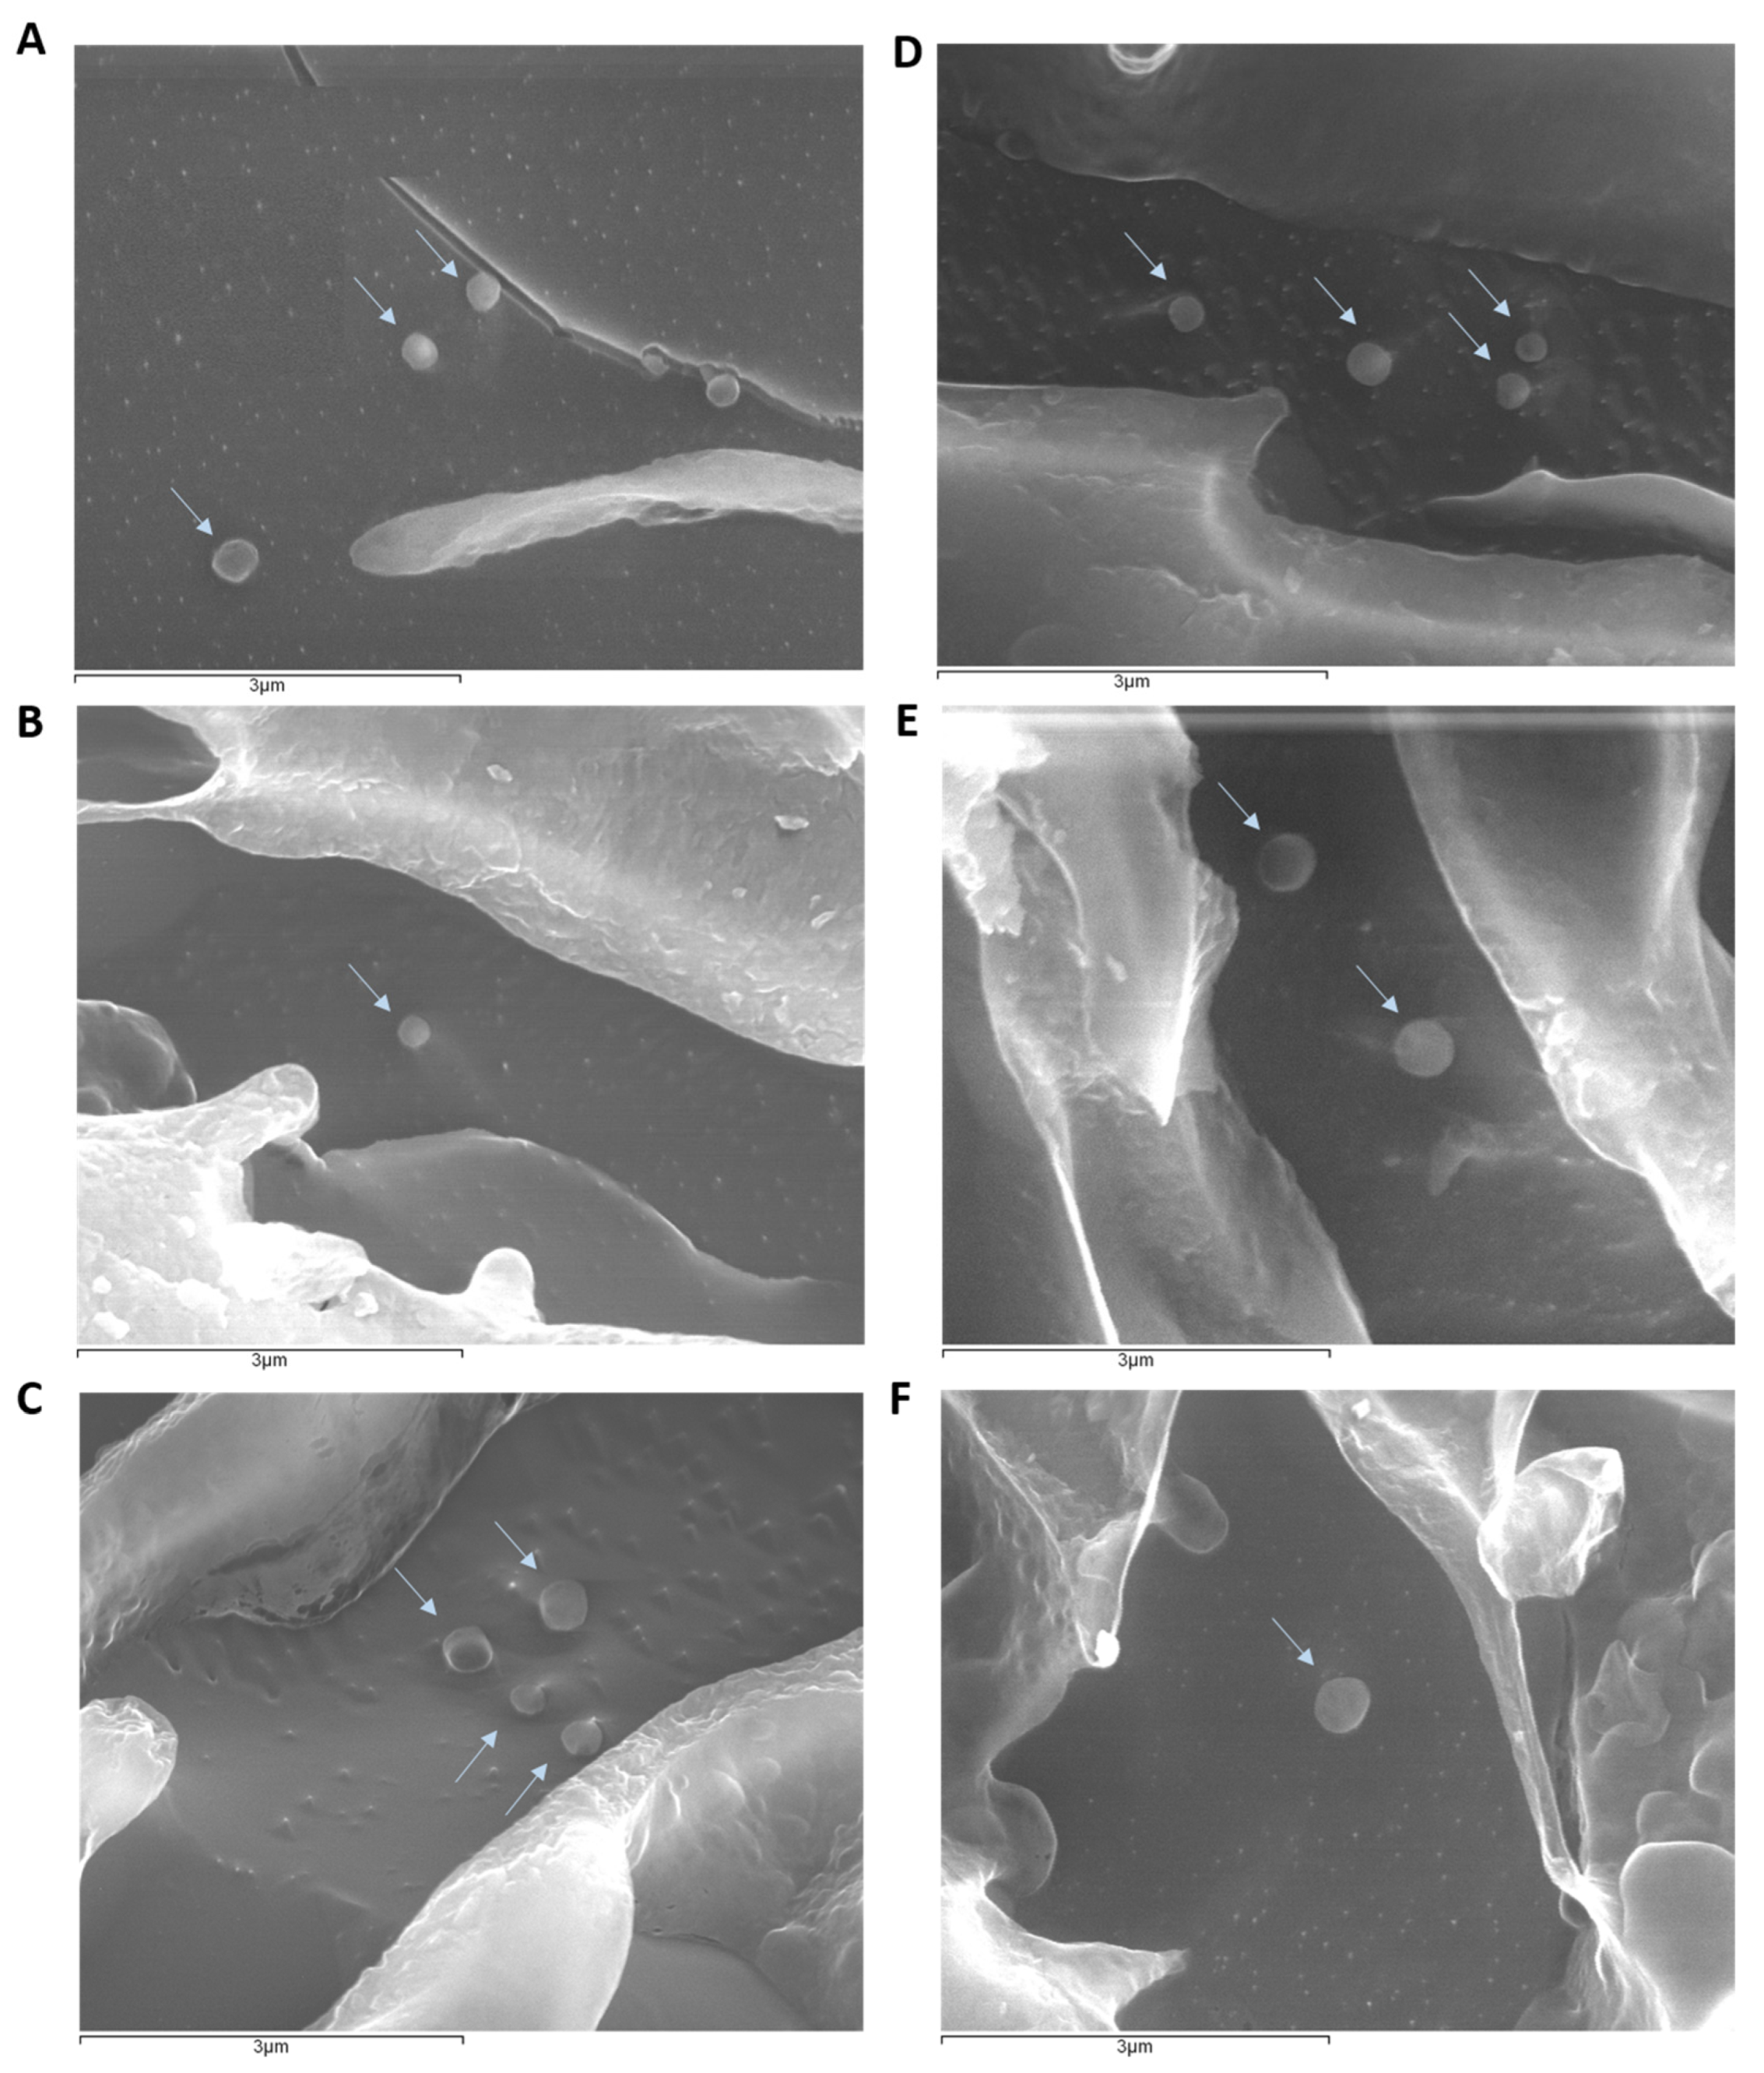

5.1.4. Cryo-Scanning Electron Microscopy (cryoSEM)